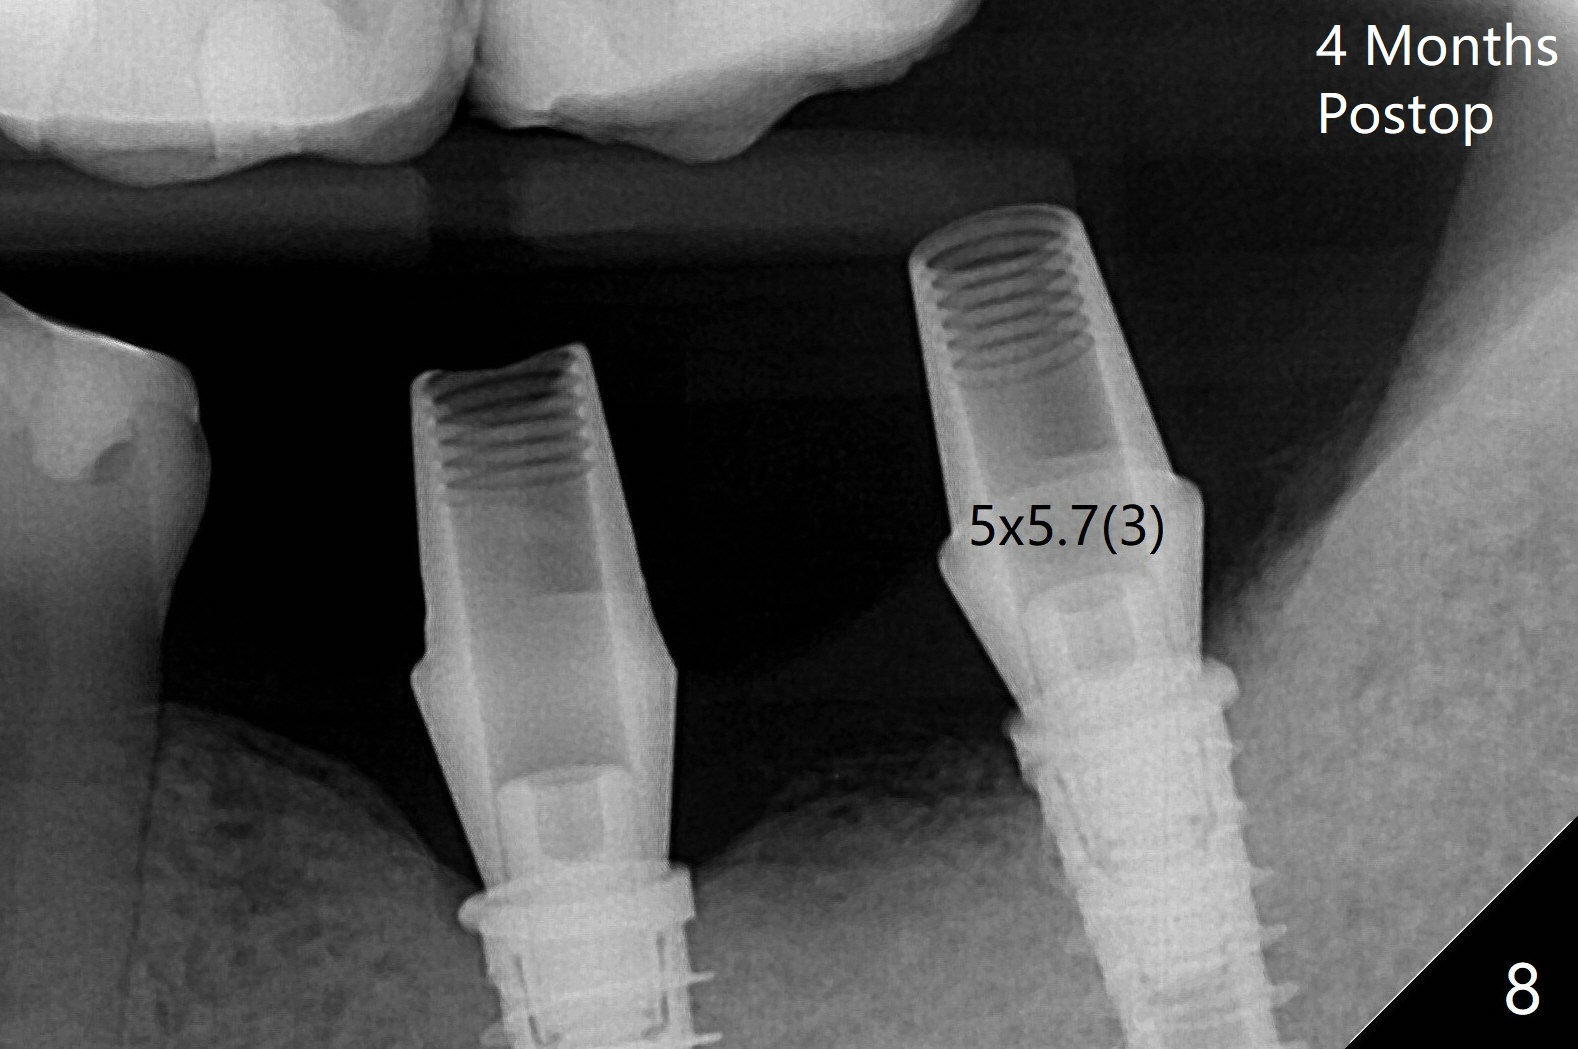

Following placement of a 4.5x11 mm implant at #19 (14 months post guide fabrication), a fixture anchor pin is placed. With stable guide, it is much easier to finish osteotomy and implant placement at #18 (Fig.1). Since the patient is nervous and sensitive to drilling, a shorter implant is placed (7 mm instead of 9 mm vs. 8.5 mm drill). The stability is unaffected because of the dense bone. After use of 5.5 mm profile drill, healing abutments (5.5x3 and 5.5x4 mm) are placed without interference. There is crestal bone loss in 3 months (Fig.2, as compared to Fig.1). Since there is more space apical to the pair abutment at #19 than that at #18, incomplete abutment seating is suspected at #19. More X-ray will be taken (Fig.3,4). In fact, it is not necessary. The space differential is also noted with healing abutments in Fig.1. BW cannot tell whether the abutment at #19 is seated or not (Fig.3). When the abutment is changed at #19 with 30 Ncm torque, the space differential remains (Fig.4, as compared Fig.2) and must be normal. The shorter implant at #18 appears not osteointegrate, since the patient feels pain when the abutment is torqued at 15 Ncm. The patient returns for temporary crown contour adjustment 1-2 weeks later. The implant at #18 is removed when the abutment screw is untightened 7 months postop; Cortical bone is placed with 6 month membrane (Fig.5). Three months later, incision will be made with reuse of the guide with fixture pin at #19. If a 4.5x9 mm implant cannot be placed, bury a short and/or narrow implant. Impression will be taken for #19 soon. In fact fixture pin cannot be seated. It appears that cancellous bone reforms, presumably low density. Underdrilling is conducted in diameter. The torque is high, but normal drilling is not carried out. The former implant exfoliated probably due to compression necrosis. The new implant is not completely seated, partially out of fear of being close to the Inferior Alveolar Canal (Fig.6). After cortical plate perforation, allograft is placed (Fig.7 *), followed by buccal flap release (periosteum underscored). In fact the implant does not have enough clearance from the Canal (red dashed line: the superior border of the Canal). The abutment at #19 returns to hold periodontal dressing in place. The implant is buried in the bone except lingual 4 months postop (Fig.8,9).